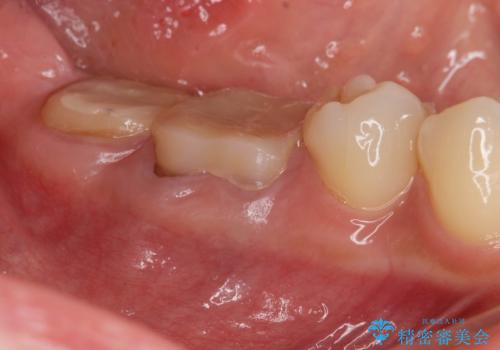

- 「笑った時に目立つ奥歯の銀歯を外して白くしたい。」と希望され来院されました。

金属のクラウンは薄く加工しても壊れないことがメリットですが、セラミッククラウンを装着するにはスペースが少なすぎ、このまま治療を進めると外れやすく壊れ易いセラミッククラウンの設計となるため、歯周外科を行い狭小なスペースの拡大を行うこととしました。